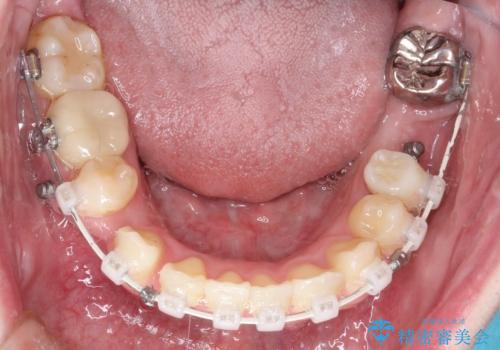

- 矯正装置

- 審美装置

ブリッジを装着している歯は動かすことができないので、矯正前に除去する必要があることがあります。

今回の場合も、ブリッジを除去して矯正後にセラミックブリッジを装着しました。